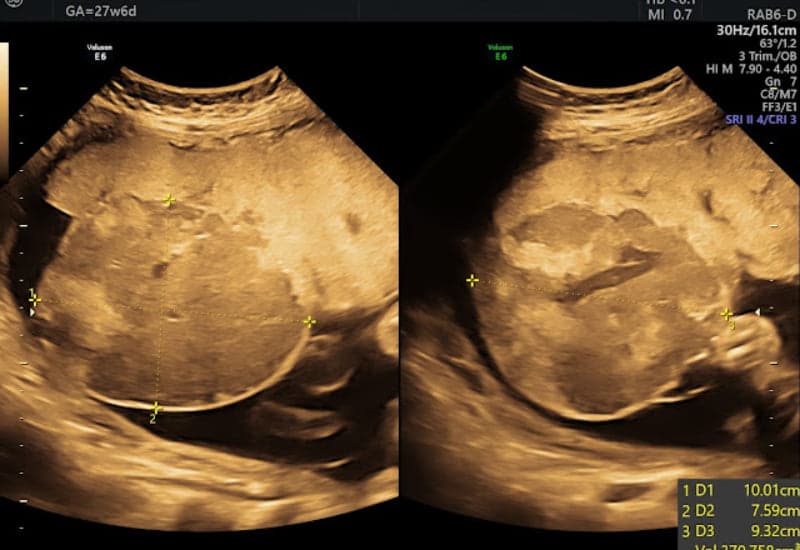

Tuy nhiên, khi khối u lớn (đặc biệt trên 6cm), nguy cơ biến chứng sẽ tăng lên. U lớn có thể làm thay đổi tuần hoàn trong bánh nhau, gây quá tải tim thai, đa ối, thai chậm tăng trưởng trong tử cung, sinh non hoặc thậm chí thai lưu. Trên siêu âm, u thường xuất hiện dưới dạng một khối tròn, ranh giới rõ, có thể quan sát được mạch máu nuôi bằng Doppler màu.